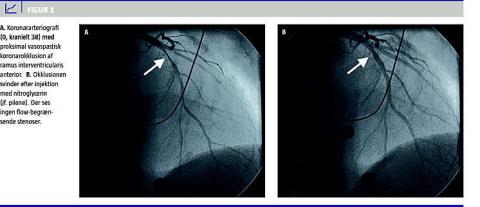

I. En 40-årig tidligere hjerterask mand, der var ryger, fik i hjemmet pludseligt indsættende kraftige brystsmerter. Umiddelbart efter redningsmandskabets ankomst fik han klinisk hjertestop. Han blev DC-konverteret fra VF til sinusrytme. Et efterfølgende elektrokardiogram (ekg) viste ST-elevation i V1-V4, og patienten blev derfor overflyttet til et hjertecenter mhp. primær perkutan koronarintervention (PCI). En akut koronararteriografi (KAG) viste en svær proksimal ramus interventricularis anterior-stenose (Figur 1 ), der svandt efter nitroglycerininjektion intrakoronart. Herefter kunne der ikke påvises flowbegrænsende stenoser. Paraklinisk var der kun let forhøjede koronarmarkører. En ekkokardiografi viste normale forhold. Patienten blev efterbehandlet med amlodipin og metropolol. Da han havde haft VF, var der indikation for implantation af en implanterbar kardioverter-defibrillator (ICD)-enhed. Ved opfølgende kontrol af ICD'en et år senere var der ikke registreret takyarytmier eller takyterapier.